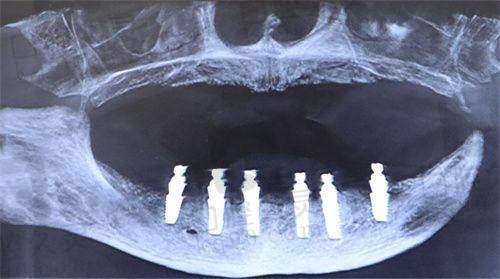

半口种植牙(All-on-4) | 40000元起 | 4颗种植体支撑半口假牙修复,快、稳 | 多颗缺失、想快捷修复半口的长者 |

全口种植牙(All-on-6或All-on-8) | 80000元起 | 稳定咬合,解决全方面缺牙问题 | 全口无牙或残根多、希望长久使用者 |